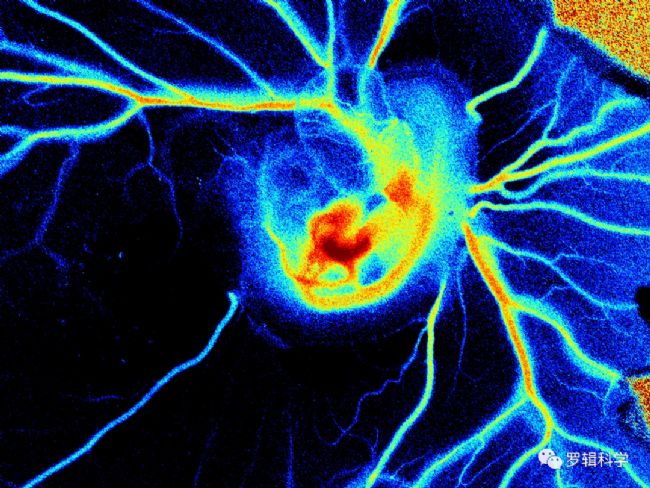

超弱生物光子成像技術實時檢測生物樣本中超弱生物光子輻射,其不但在離體腦片層面,也能在活體層面對腦皮層和深部腦區對單個神經細胞進行在體超弱生物光子成像,從而解析在給定的外部刺激或活體本身的狀態改變下導致單神經細胞或神經環路跨突觸的生物光子活動狀態變化,并對神經信號傳遞模式進行分析。經分析發現,給定刺激的神經細胞其被檢測的生物光子的強度和光譜有關,紅光有更明顯的傳播優勢,但與其膜電位水平無明顯的關聯。這一結果為生物光子與神經信息傳遞上的最新發現。

腦科學研究方面,超弱生物光子成像可在腦片和活體層面對單神經細胞狀態和神經環路跨突觸的信號傳遞進行解析。

眼視覺研究方面:最新研究發現皮層神經細胞的活動是動物對內外環境活動變化的直接反應,而我們觀察到的生物光子的活動改變,一方面反映視覺信息通過視覺通路傳遞到了皮質,另一方面其改變的模式提示生物光子可能參與視覺運動回路的信息編碼過程。